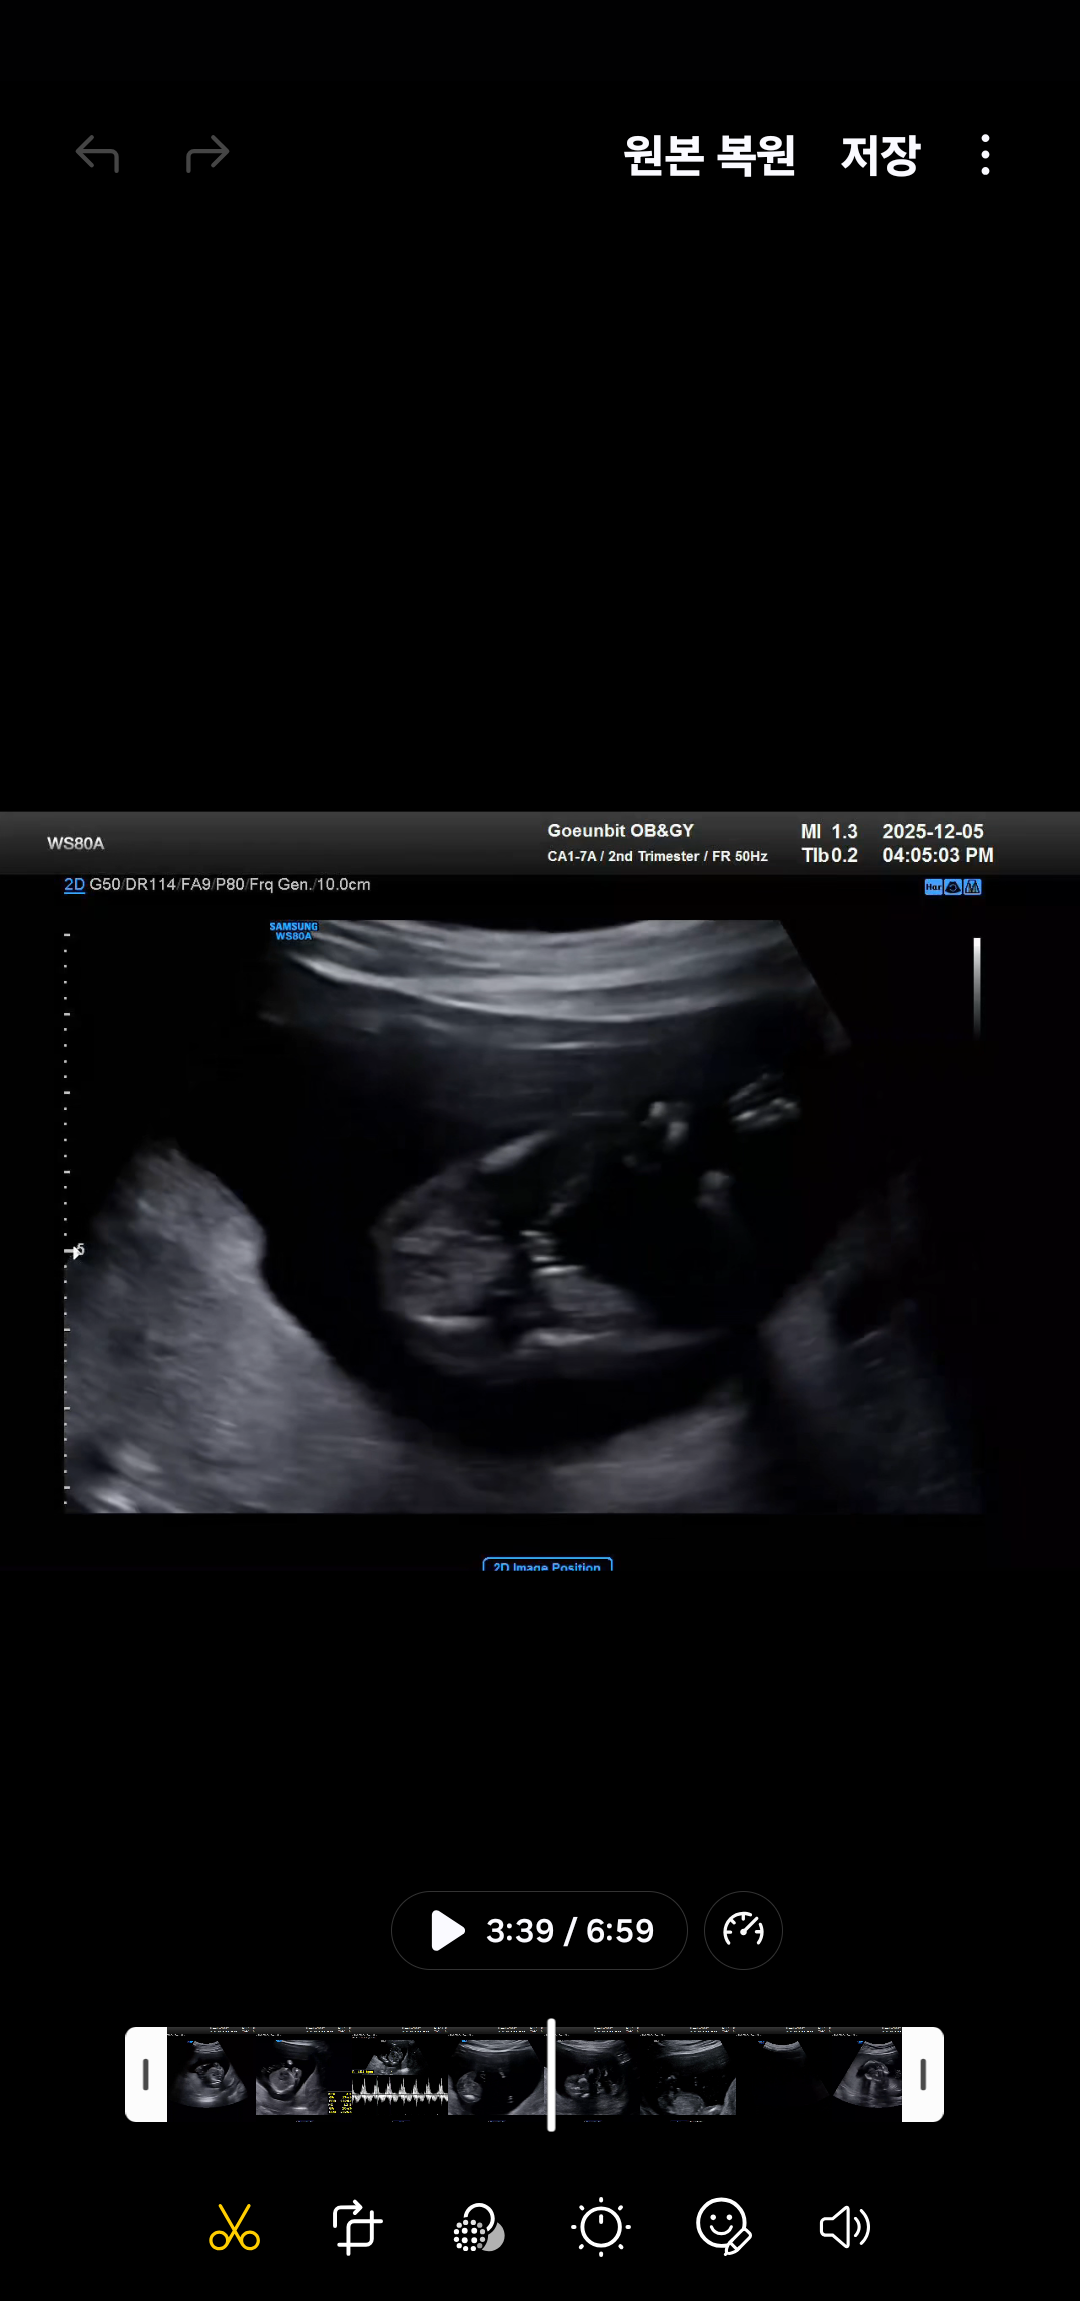

16주차때 성별 확인했는데

여아라 하는데 다들 뭐같으세요?